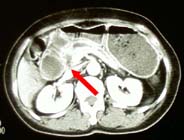

ヘリカルCT連続画像 |

ヘリカルCT拡大画像 |